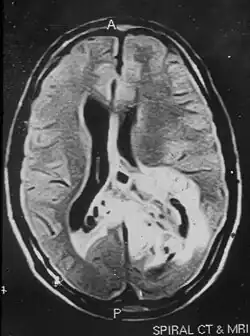

Due to the large range of causes that lead to micropsia, diagnosis varies among cases. Computed tomography (CT) and magnetic resonance imaging (MRI) may find lesions and hypodense areas in the temporal and occipital lobes.[4] MRI and CT techniques are able to rule out lesions as the cause for micropsia, but are not sufficient to diagnose the most common causes.

Non-contrast magnetic resonance imaging showing hyper-intense lesion involving the left temporal and parieto-occipital regions. The tumor is crossing the midline to the right parietal region.

An MRI image of a brain tumor occupying the left temporal and parieto-occipital regions of the brain.

Brain lesions

Micropsia is sometimes seen in individuals with brain infarctions. The damaged side of the brain conveys size information that contradicts the size information conveyed by the other side of the brain. This causes a contradiction to arise between the true perception of an object's size and the smaller perception of the object, and micropsic bias ultimately causes the individual to experience micropsia. Lesions affecting other parts of the extracerebral visual pathways can also cause micropsia.[3]